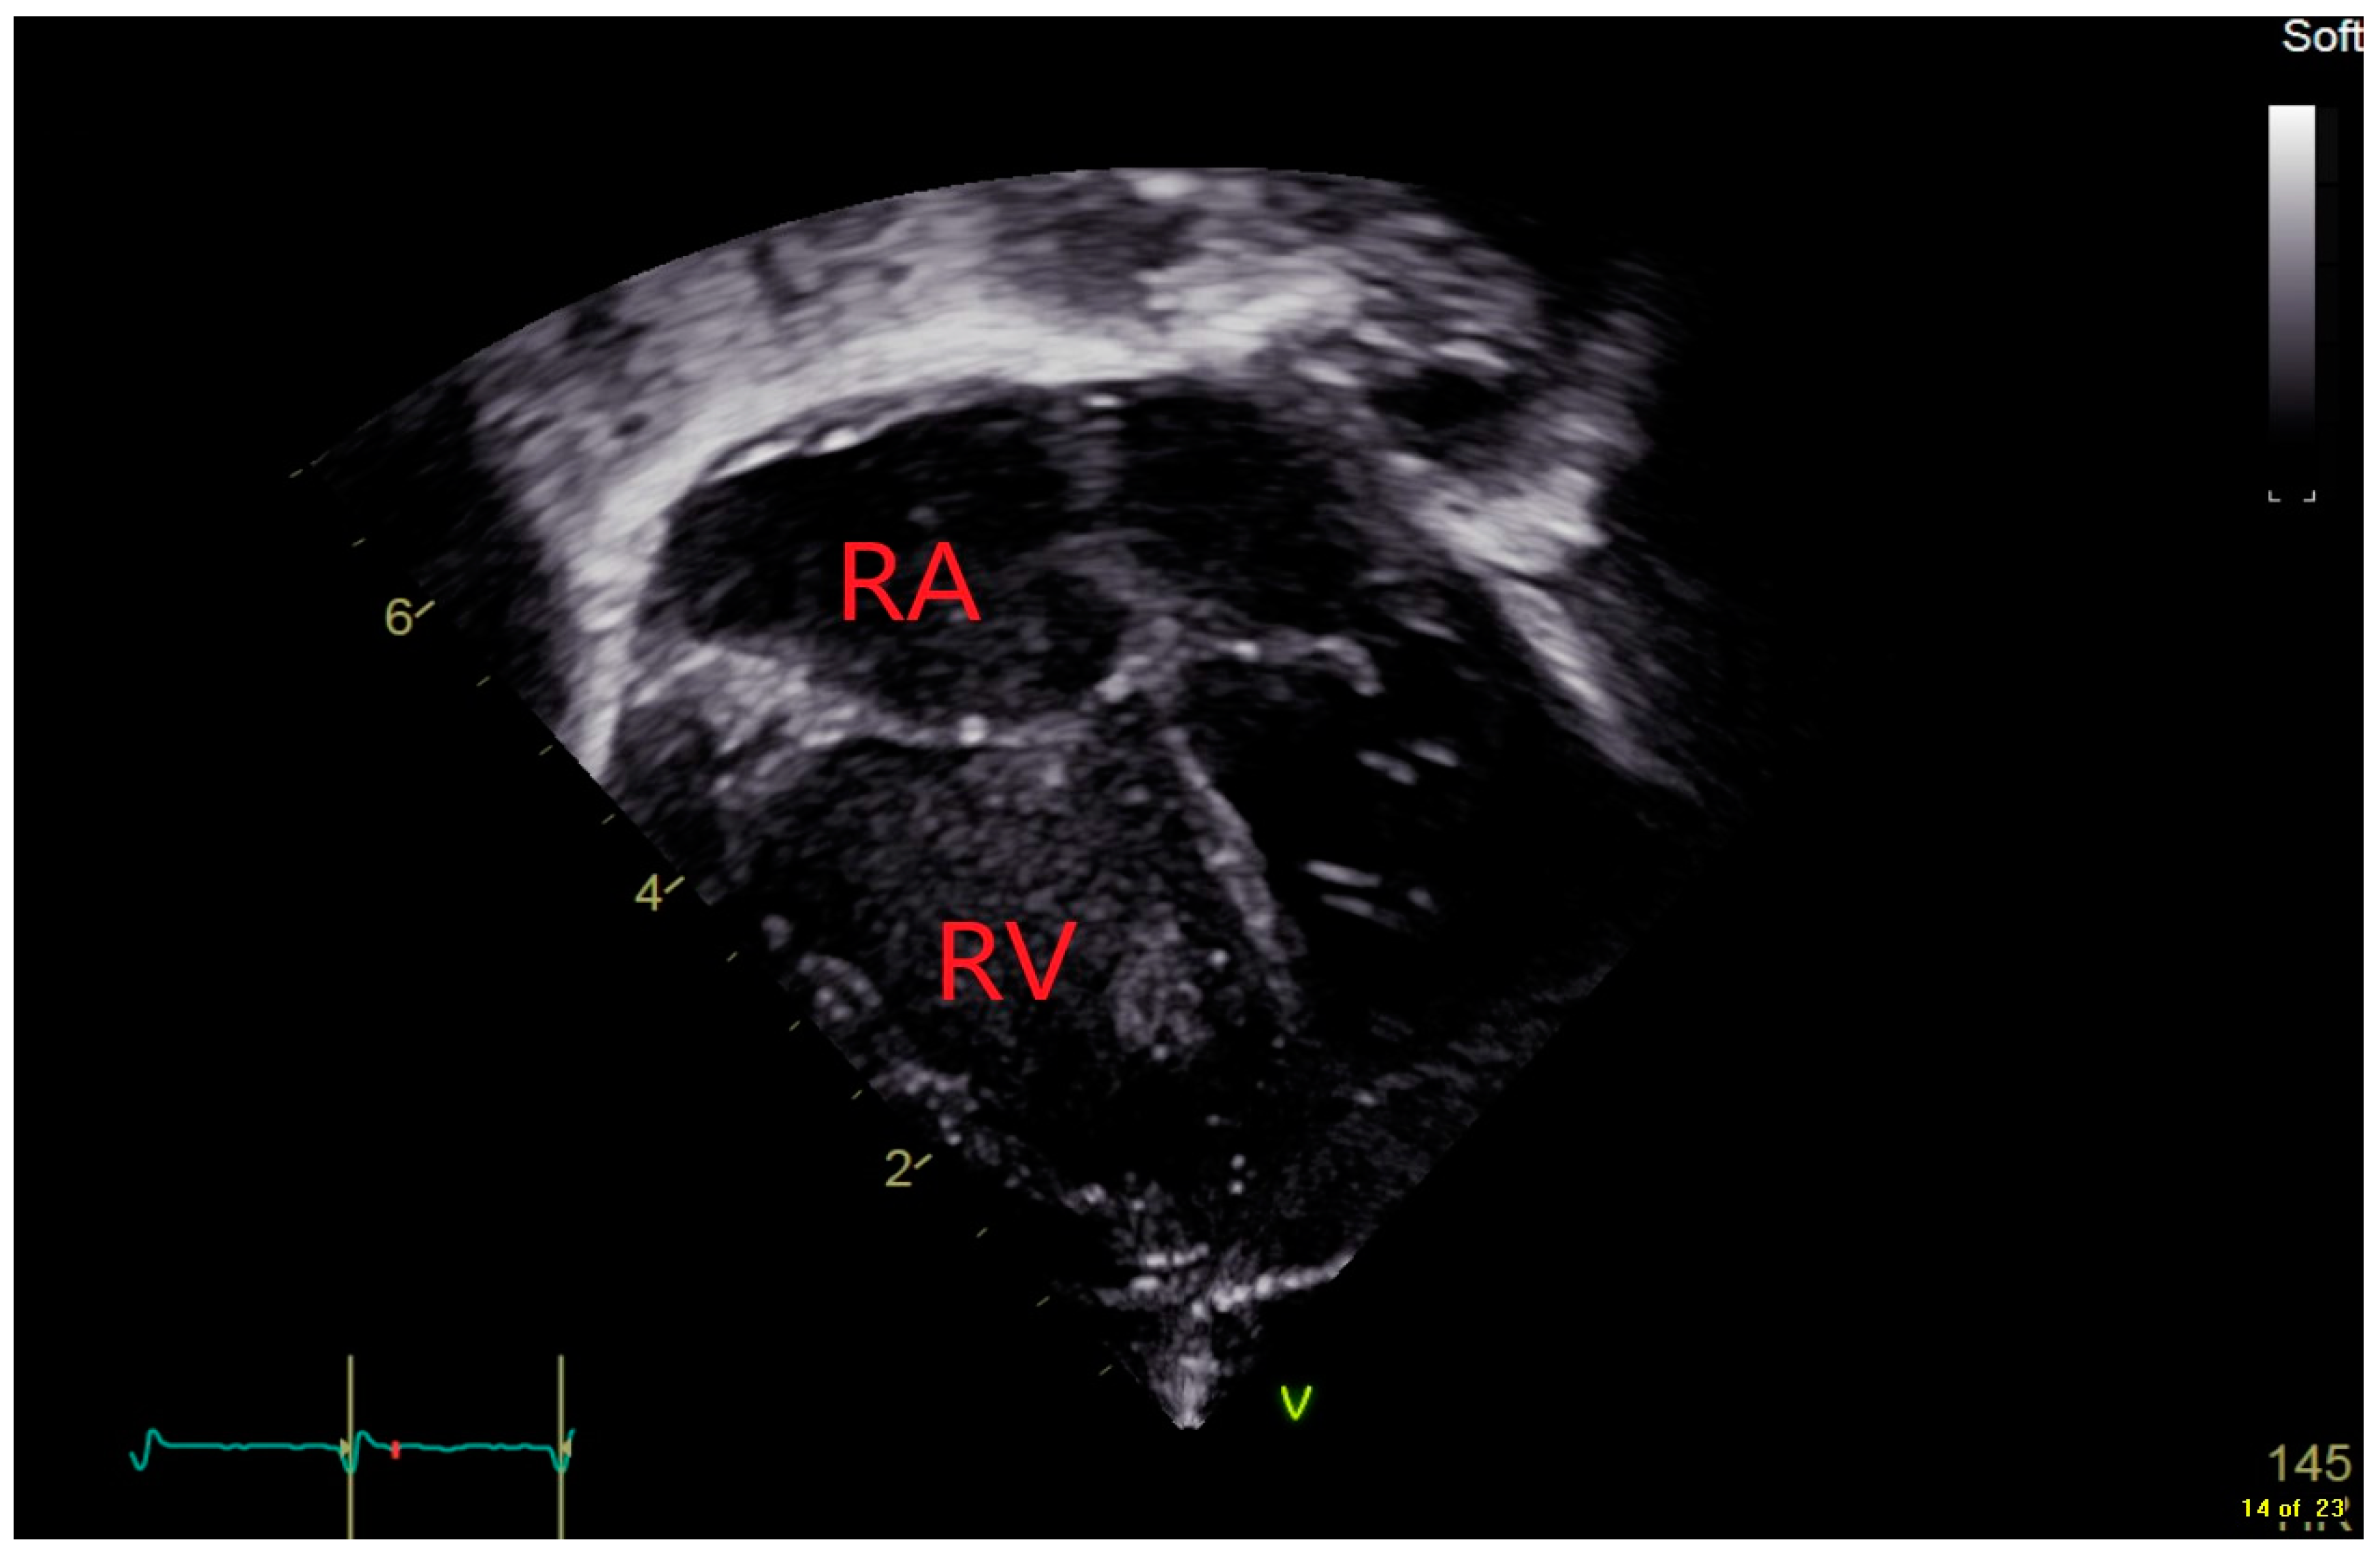

| RA | Right Atrium |

| RV | Right Ventricle |

| TRJV- | Tricuspid Regurgitant Jet Velocity |